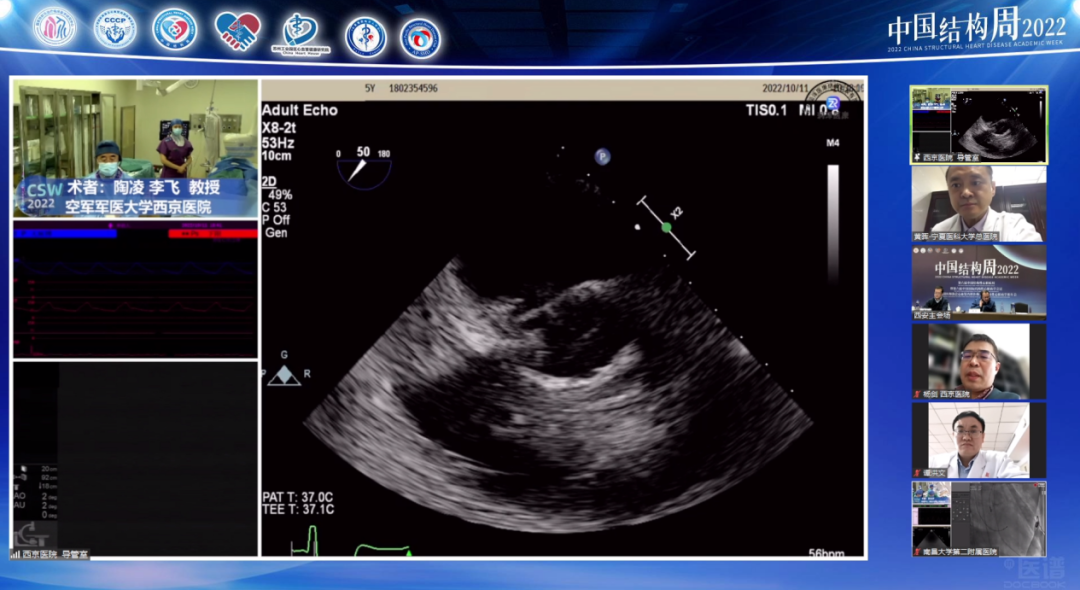

空军军医大学西京医院陶凌教授团队(术者:李飞教授)带来一例感染性心内膜炎重度AS患者。

病例介绍:男性患者65岁,主诉劳累后胸痛、胸闷、气短10余年,加重7月余。

患者10余年前心脏彩超检查示主动脉瓣狭窄,7月前气短症状明显加重,夜间端坐呼吸,心脏彩超示主动脉瓣重度狭窄。合并症2型糖尿病病史5年,脑梗死病史2月余,泌尿系感染1月余、外周血管溃疡。

手术策略主要讨论如下:

血管存在溃疡、夹层,入路及外周并发症如何处理?

Type1型二叶瓣,严重偏心性钙化病变,瓣膜选择及释放高度如何?

预扩张及后扩张策略?

手术可能存在的并发症及应对策略?

针对本例患者,术者团队介绍了特殊情况,食道超声检查示无冠窦窦壁有囊性结构,考虑存在感染,血流通过无冠窦窦壁喷射到囊腔里面,随后询问病史患者自述有泌尿系感染1月余,故考虑合并感染性心内膜炎,囊性结构是陈旧性赘生物。有专家认为患者有脑梗死病史2月余,系囊性赘生物脱落所致。

与会专家针对食道超声发现的囊性结构展开激烈探讨,对于泌尿系感染和脑梗死的病因认为是赘生物脱落所致,在此情况下,建议该患者不太适合TAVR手术。李飞教授同意现场探讨内容,下一步策略计划再次评估CTA,局部采血后血培养,核磁明确,考虑到患者心衰严重,首先保守治疗后,选择SAVR(外科主动脉瓣置换术)还是抗炎后TAVR具体情况深入分析后在做抉择。但有专家更倾向于外科开胸换瓣,可以进一步分析病理。